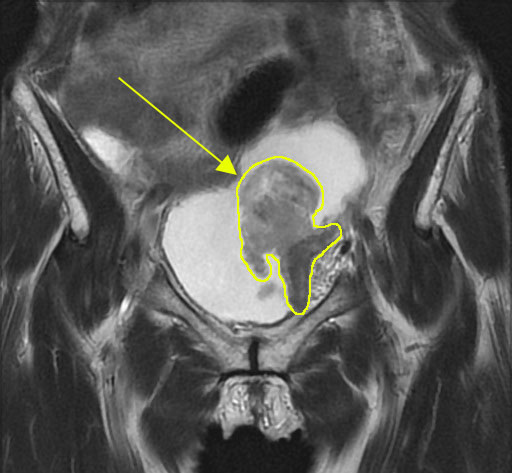

⑤ CT・MRI検査

腫瘍の大きさや浸潤度、リンパ節、遠隔転移の有無検索に有用な検査します。

膀胱がんCT

※膀胱がんのCT画像